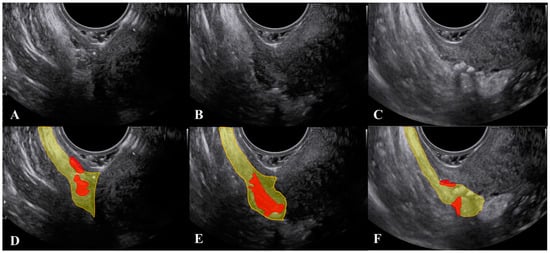

2.1. The Uterosacral Ligament

2.2. The Parametrium

2.3. The Paracervix

3. What Ultrasound Should Investigate and Detect

4. Anatomical Considerations and Surgical Implications